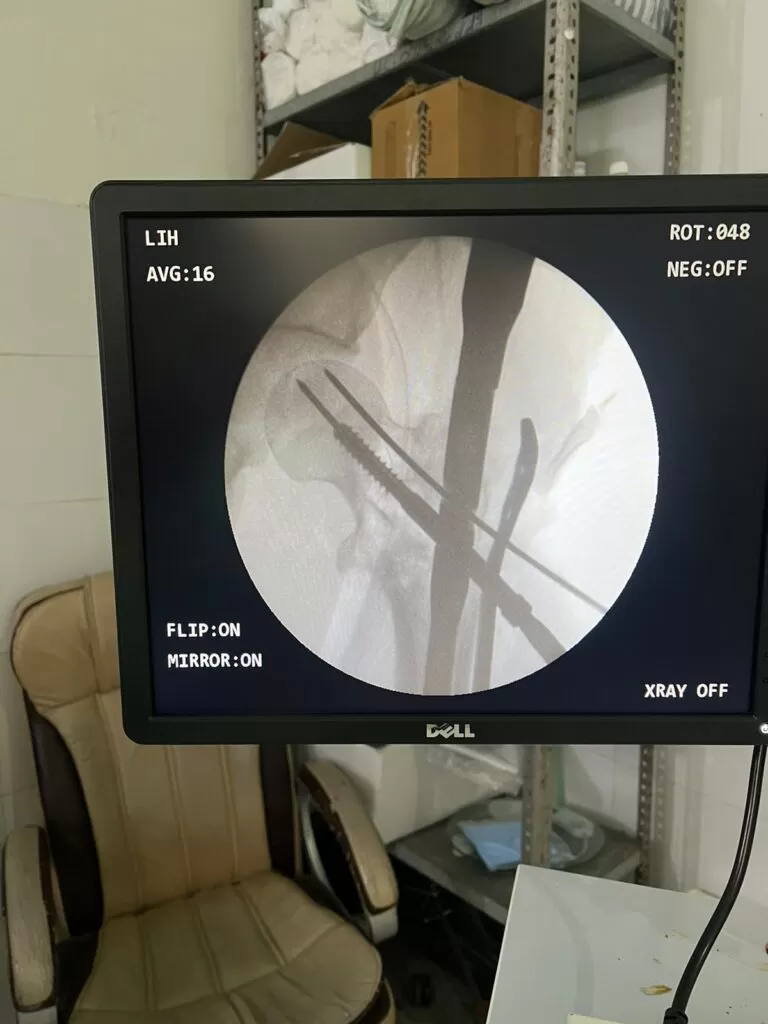

Mr. Rahisuddin

Name: Mr. Rahisuddin

Date of Operation: 04 May 2024

Age: 25 Years